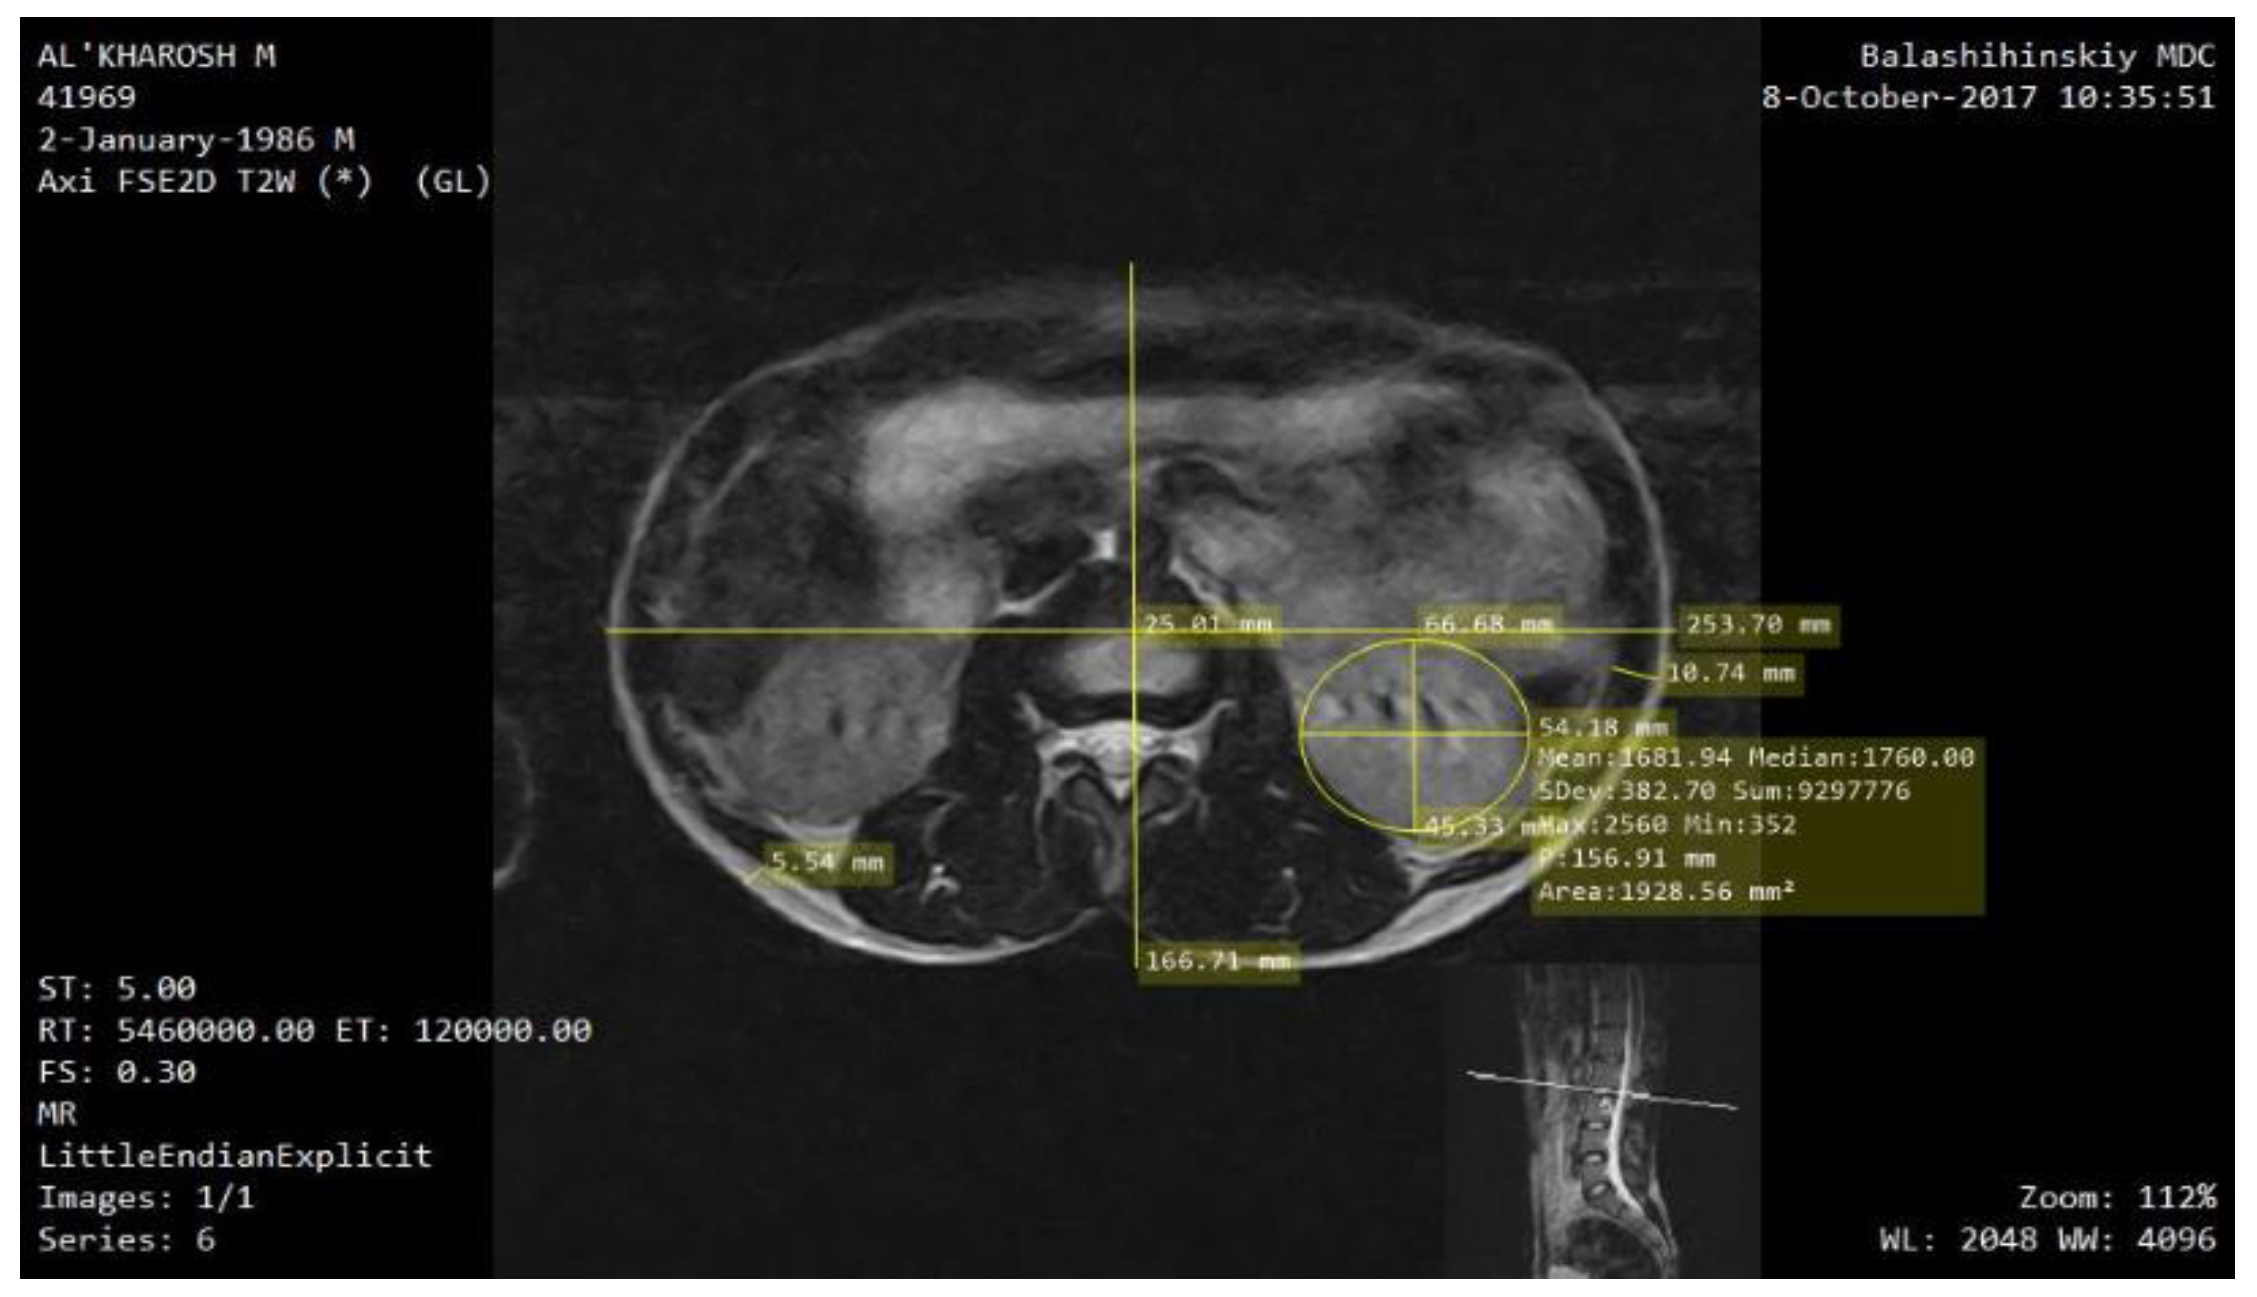

| Model Parameters | Value [mm] |

|---|---|

| 2a1 | 253.7 |

| 2b1 | 166.71 |

| hsubc | 5.54 |

| hm | 10.74 |

| hc | 5 |